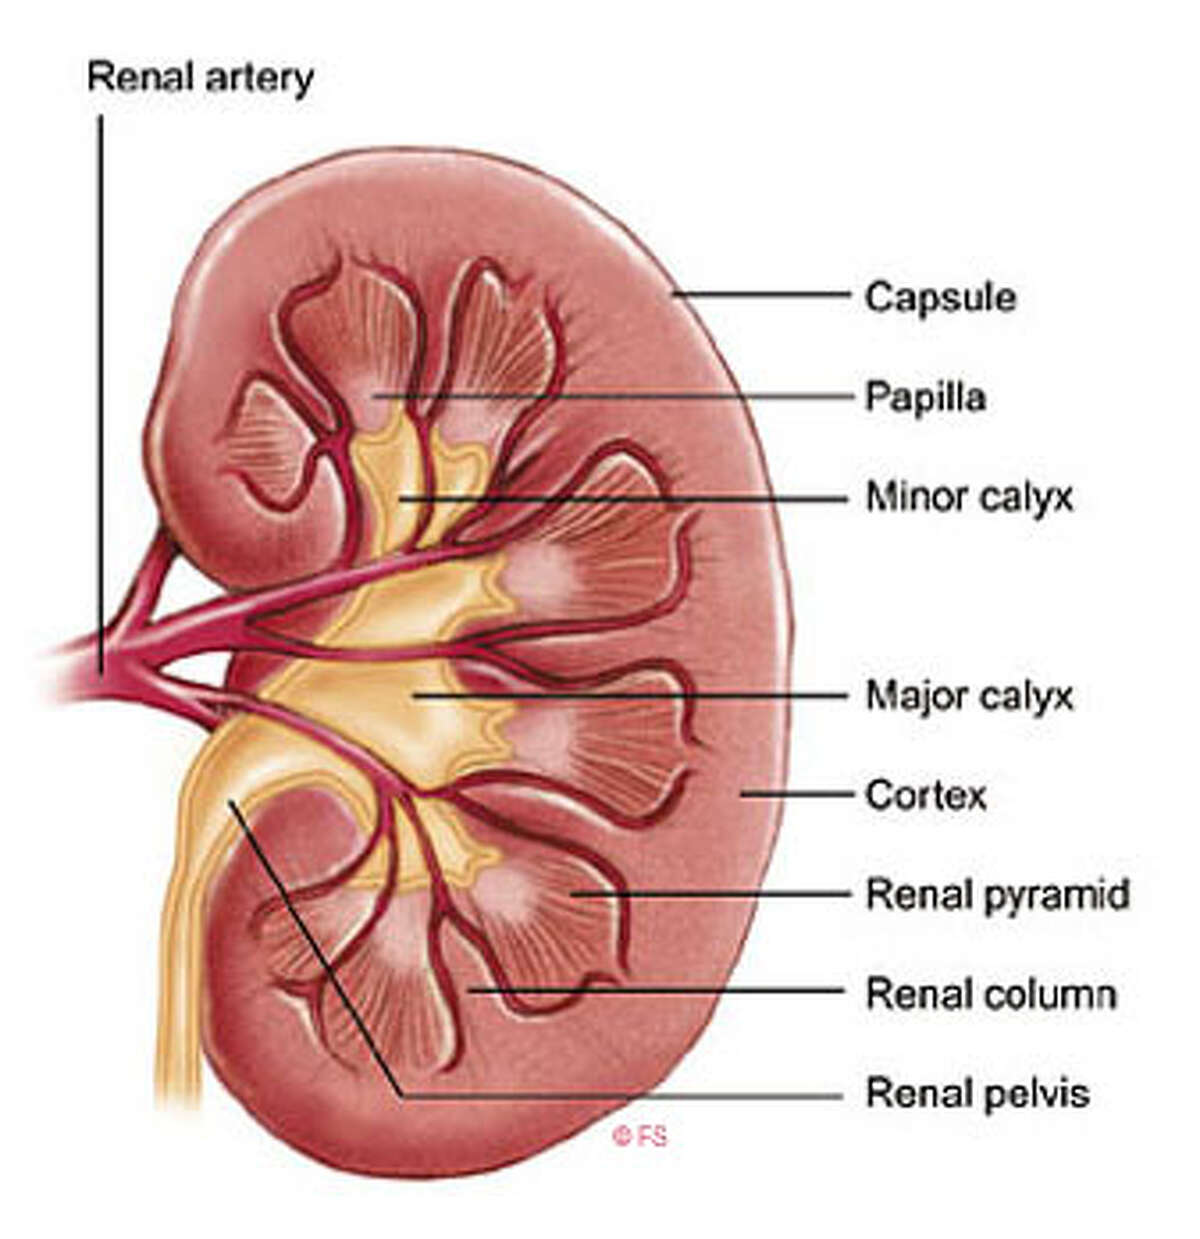

Интраренальная лоханка: рентгеновские снимки и примеры